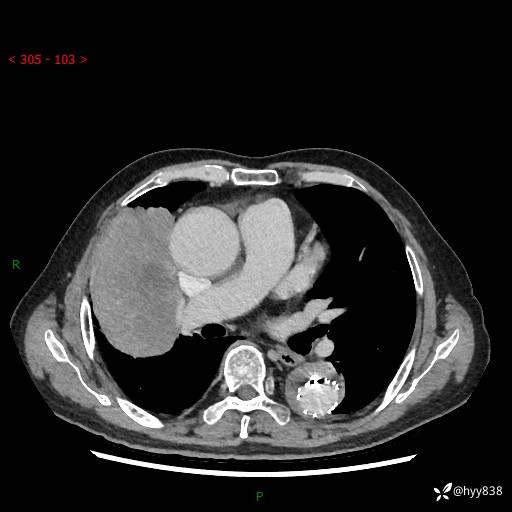

增强动脉期